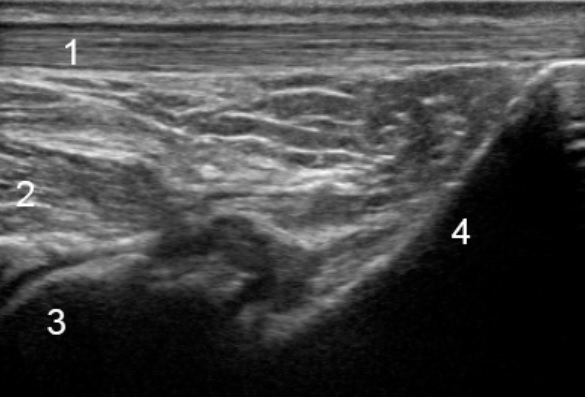

后踝部纵向 1 图像